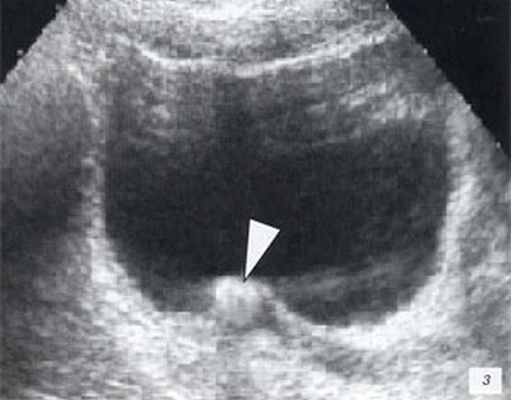

и хронического пиелонефрита, гнойных поражений почек). При мочекаменной болезни

УЗИ почек высокоэффективна в выявлении конкрементов.

При УЗИ визуализируются камни любого химического состава, в то время для

рентгенологических методик камни, состоящие из мочевой кислоты, остаются невидимыми.

Также УЗИ информативно при определении уровня локализации конкремента,

уродинамических осложнениях мочекаменной болезни – обструкции, супрастенотическом

расширении мочевых путей.